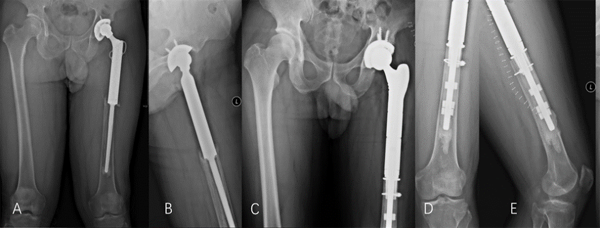

女,45岁,左股骨近端骨肉瘤行左股骨近端切除+左股骨近端肿瘤假体置换术后14年,可见假体松动下沉,采用沉管多孔金属圈(D)重建内壁后,患者目前随访3年余,假体固定良好,断层造影箭头指示处(K)可见多孔金属圈有骨长入,临床效果满意。

男,45岁,左股骨近端组织细胞肉瘤行左股骨近端切除+左股骨近端肿瘤假体置换术后7年,可见假体松动下沉,采用“沉管” 骨内壁重建技术后,患者目前随访2年余,假体固定良好,临床效果满意。